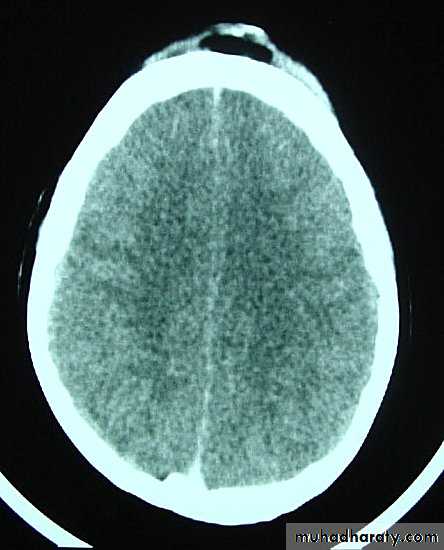

1. Brain Oedema (Cerebral Swelling)

Can be local (around a haematoma) or diffuse.

It is due to intracellular or extracellular accumulation of fluid.

It leads to raised intracranial pressure, which itself causes problems.

It is more common and more dangerous in children.